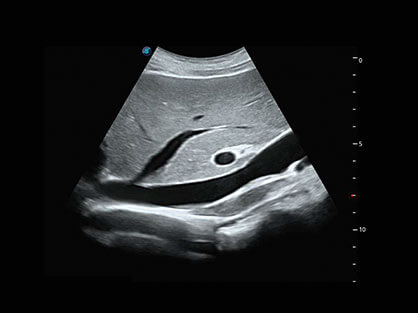

自动识别穿刺针进行声束智能偏转 手动修正多档调节 提高一次穿刺成功率